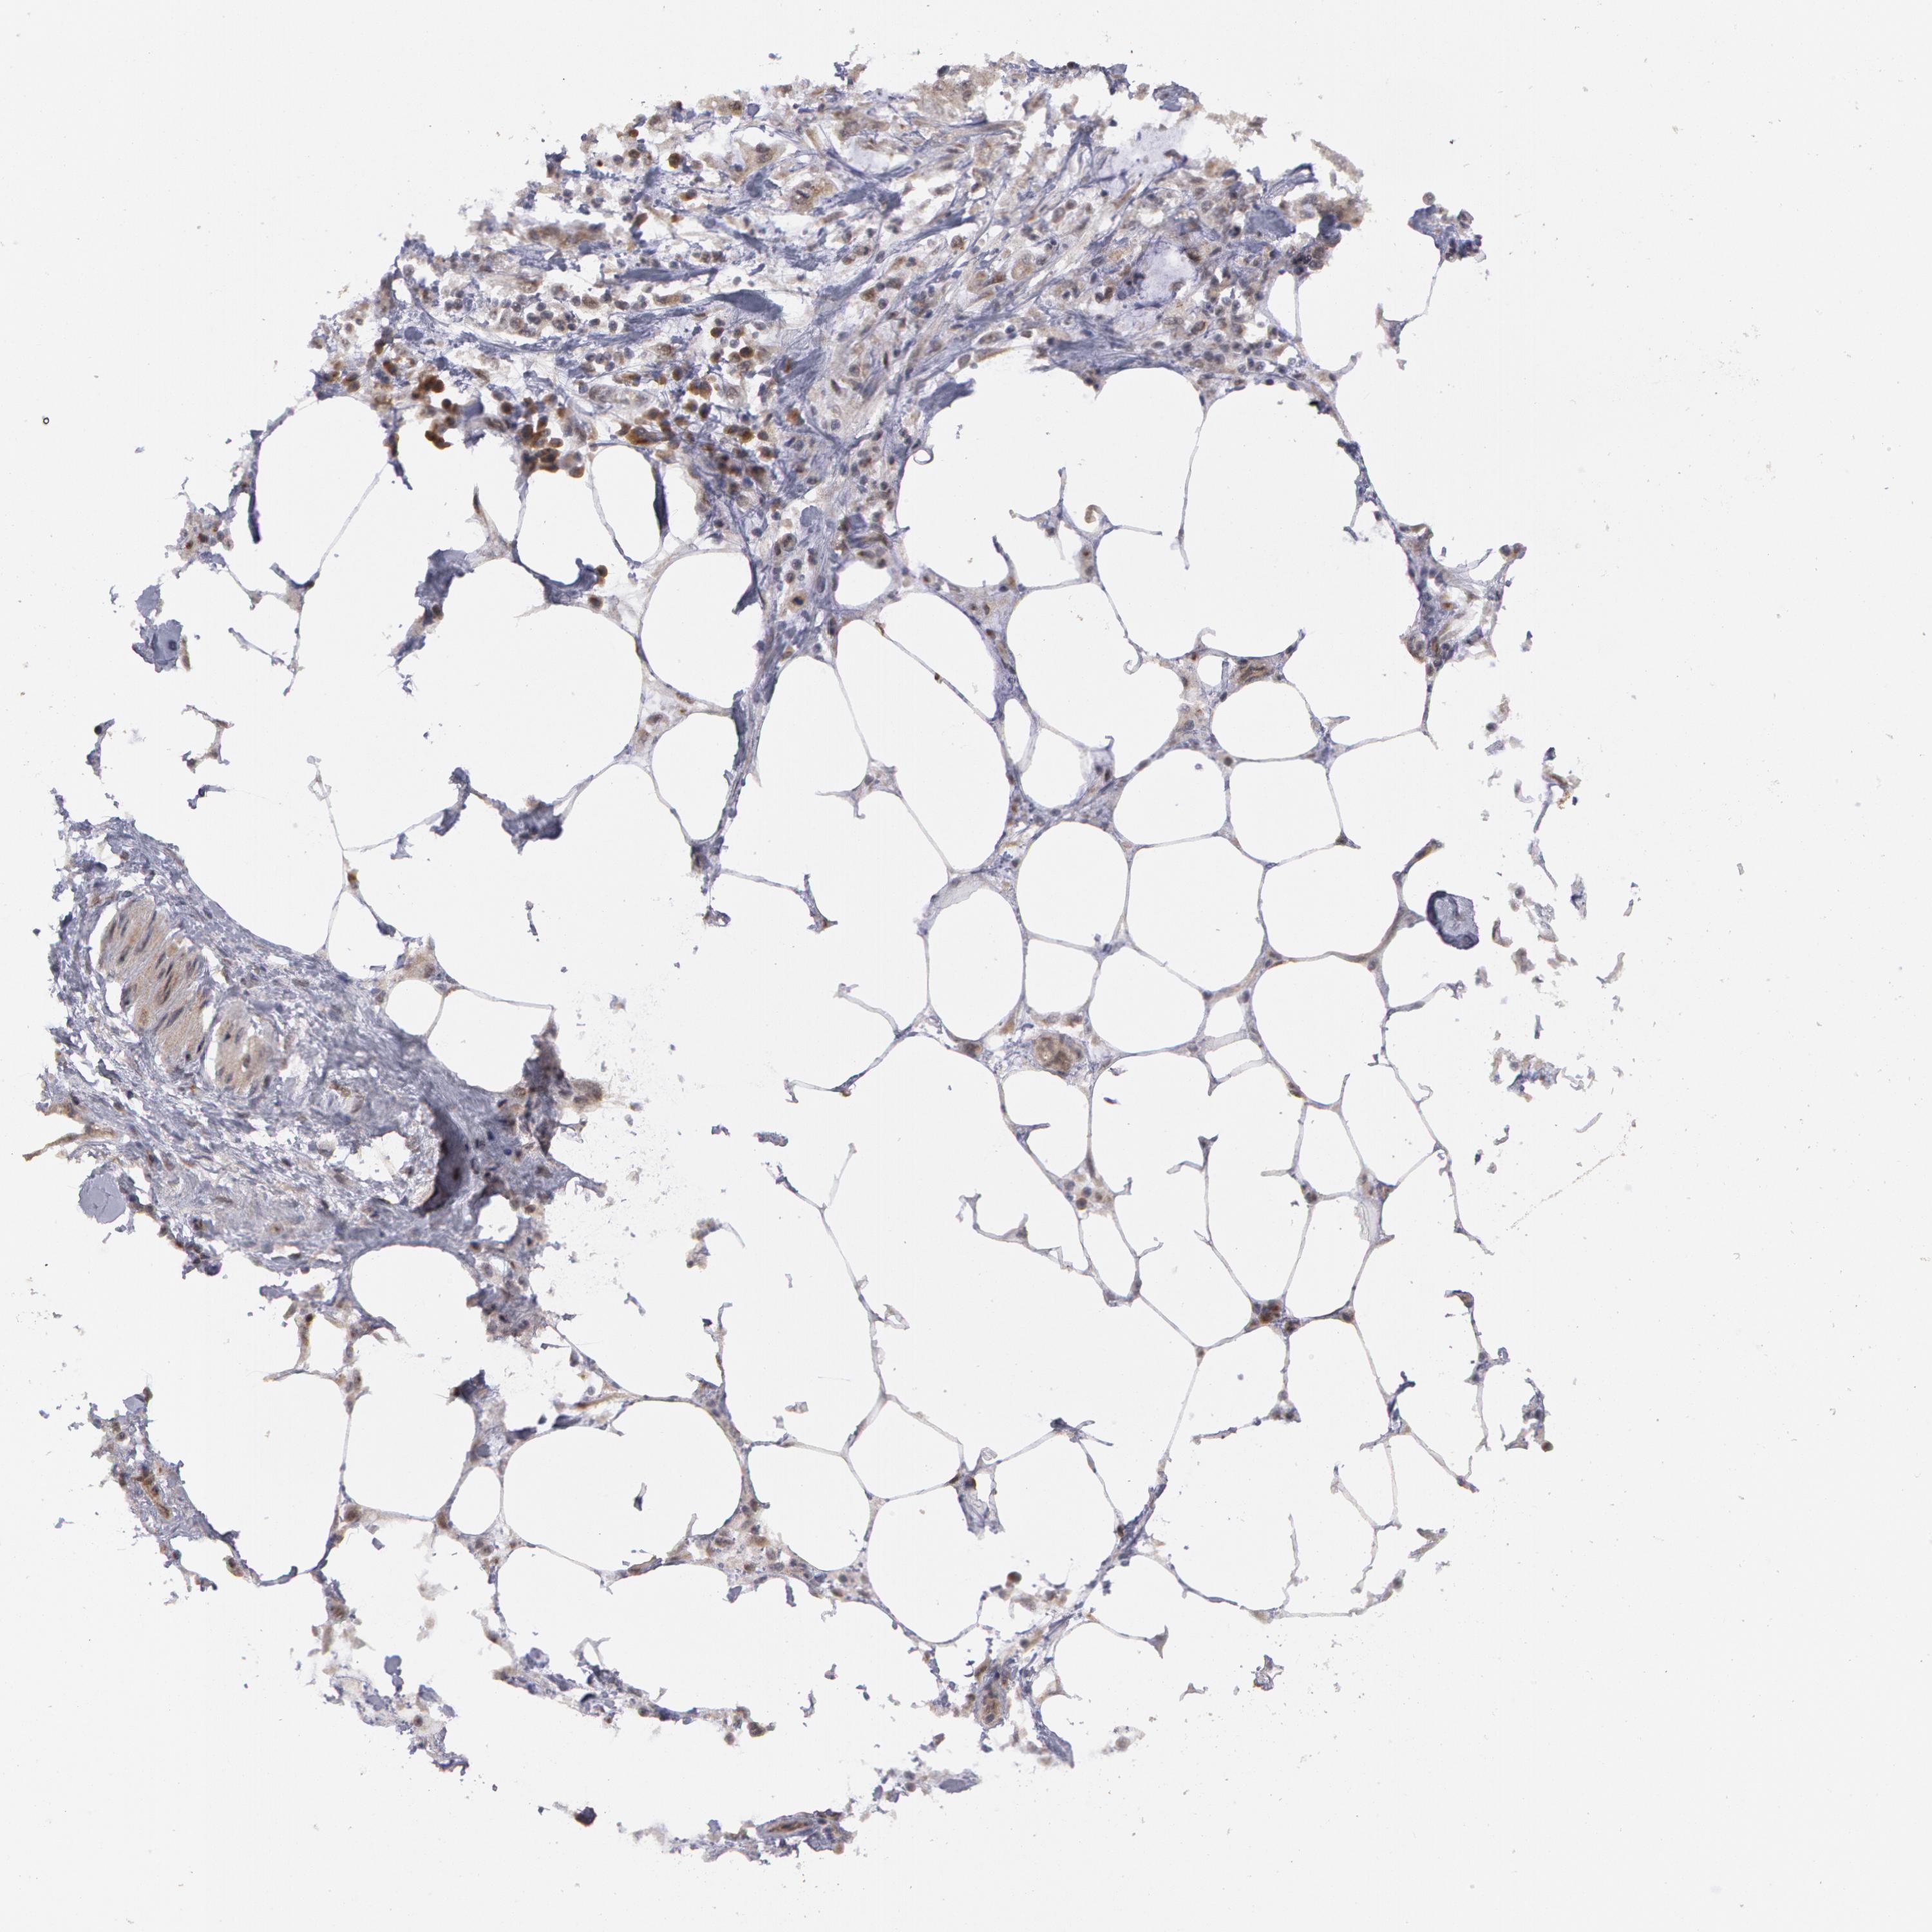

PANCREATIC CANCER - Protein expressioni

A mouse-over function shows sample information and annotation data. Click on an image to view it in a full screen mode. Samples can be filtered based on level of antibody staining by selecting one or several of the following categories: high, medium, low and not detected. The assay and annotation is described here.

Note that samples used for immunohistochemistry by the Human Protein Atlas do not correspond to samples in the TCGA dataset.

Antibody stainingi

Antibody staining in the annotated cell types in the current human tissue is reported as not detected, low, medium, or high, based on conventional immunohistochemistry profiling in selected tissues. This score is based on the combination of the staining intensity and fraction of stained cells.

Each image is clickable and will lead to virtual microscopy that enables deeper exploration of all samples and also displays staining intensity scores, fraction scores and subcellular localization as well as patient and tissue information for each sample.

Antibody HPA001358

Staining

High

Medium

Low

Not detected

Intensity

Strong

Moderate

Weak

Negative

Quantity

>75%

75%-25%

<25%

None

Location

Nuclear

Cytoplasmic/membranous

Cytoplasmic/membranous,nuclear

Adenocarcinoma, NOS